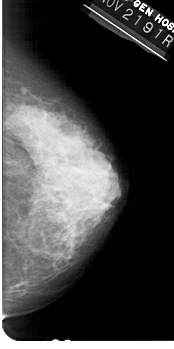

A_1449_1.LEFT_MLO

LEFT_MLO LINES 5491 PIXELS_PER_LINE 2776 BITS_PER_PIXEL 12 RESOLUTION 43.5 OVERLAY